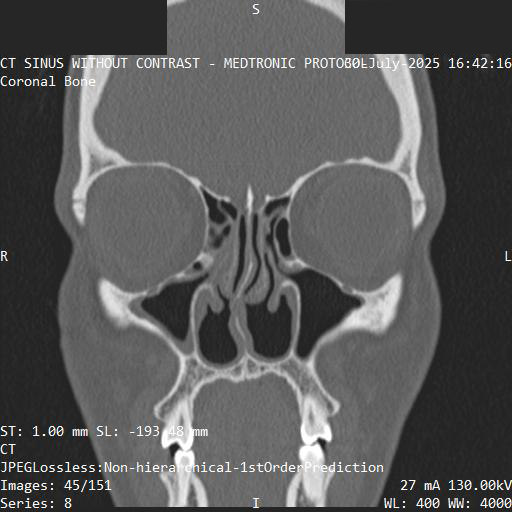

A single cross section from the imaging.